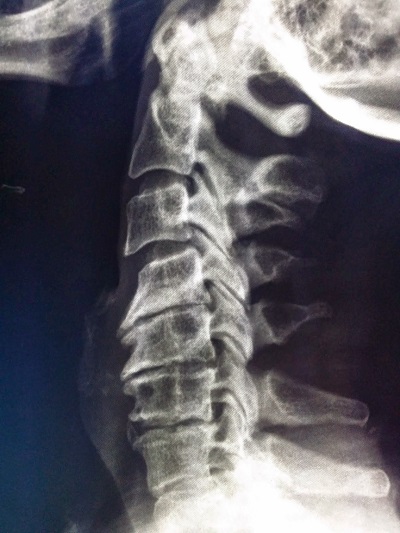

การวินิจฉัยโรคเป็นการวิเคราะห์ข้อมูลจากการซักประวัติอาการปวดของผู้ป่วย ร่วมกับการตรวจร่างกายของแพทย์ ซึ่งถ้ามีอาการปวดมากแพทย์อาจส่งตรวจภาพถ่ายเอกซเรย์บริเวณกระดูกต้นคอ ซึ่งมักจะพบว่ามีการเสื่อมของหมอนรองกระดูกต้นคอ สังเกตได้จากความสูงของหมอนรองกระดูกสันหลังมีขนาดลดลง เพราะปกติหมอนรองกระดูกมีองค์ประกอบส่วนใหญ่เป็นน้ำ และเมื่อเกิดกระบวนการเสื่อมจะทำให้ปริมาณน้ำในหมอนรองกระดูกลดปริมาณลง และในบางครั้งอาจเกิดการเคลื่อนของหมอนรองกระดูกชั้นในออกมากดทับเส้นประสาท นอกจากนี้อาจจะพบลักษณะของกระดูกงอกออกไปกดทับเส้นประสาทร่วมด้วย ในบางกรณีถ้าผู้ป่วยมีอาการเรื้อรัง อาการปวดไม่บรรเทาลงหลังจากการให้การรักษาที่ถูกต้องอย่างต่อเนื่อง แพทย์ผู้ทำการรักษาอาจจะพิจารณาส่งผู้ป่วยไปตรวจด้วยภาพคลื่นแม่เหล็กไฟฟ้า (MRI) ซึ่งจะช่วยแสดงรอยโรคได้ชัดเจนมากกว่าภาพถ่ายรังสีธรรมดา